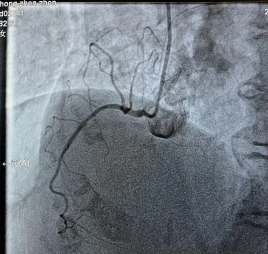

前降支未见明显狭窄